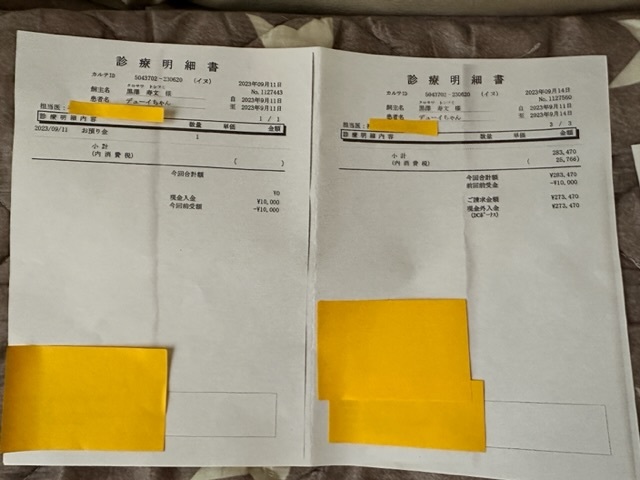

クラウドファンディング目標金額690.000円

実施済みの外科的手術や皮膚トラブルによる

通院、検査、手術費用など

477.866円

※内、保険が下りた金額36.376円は費用から差し引いてあります。

※上記は大学病院で頂いた診断書

※下記は初診かつ、会陰形成術をして頂く動物病院より発行して頂いた診断書、治療計画書

実際にかかった治療費

★

★

★

★

大学病院での検査

大学病院での手術、入院費

術後抜糸